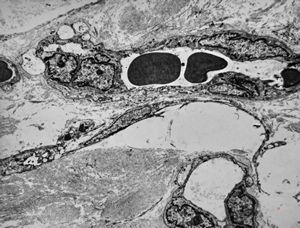

F,41y. | synovial metaplasia - capsule of implantate